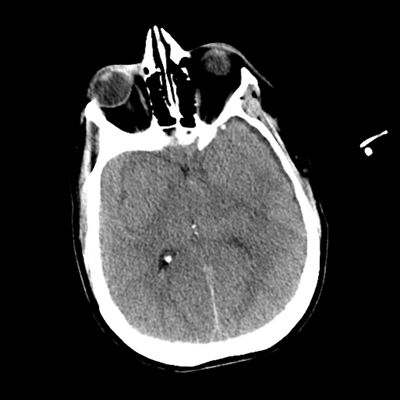

CTA head (MIP)

Starting with the non-contrast head CT, we can appreciate that there's actually not much residual subarachnoid blood at all; it's essentially all resorbed already (and cleared through the EVD). The ventricular caliber is stable. With the CTA head (for convenience's sake, the MIPs were shown), it's subtle, but we can see that the PCAs on each side are not as smooth and regular. The right MCA, starting at the bifurcation, also becomes narrower. This is [radiographic] vasospasm. Now, looking at the CT perfusion-- specifically, the Tmax (MTT) map that were selected-- there's clearly some abnormality within the bilateral cerebellar hemispheres and occipital lobes. Not a lot, but it's there. Delving further into this map, we can appreciate that the areas of abnormality are mainly green, signifying that these areas have Tmax > 6 seconds. This is the threshold that is specific, not sensitive, for vasospasm.

Putting this all together, we have thus identified radiographic vasospasm with the vessel imaging, with perfusion abnormalities that are concordant with it. Does the area of vasospasm and hypoperfusion correlate with the patient's clinical exam?

Yes! It does. The patient had a decline in level of consciousness with diffuse loss of motor function. This does correlate to the basilar territory. (Alternatively, bilateral MCA vasospasm could also be responsible, reminding us that a decline in consciousness could technically be focal/multifocal.) Thus, we can say that this patient does have clinical vasospasm. Whether this will develop into irreversible DCI remains to be seen; at least, the non-contrast head CT and the other portions of the CT perfusion (not shown) currently don't [yet] suggest infarction.